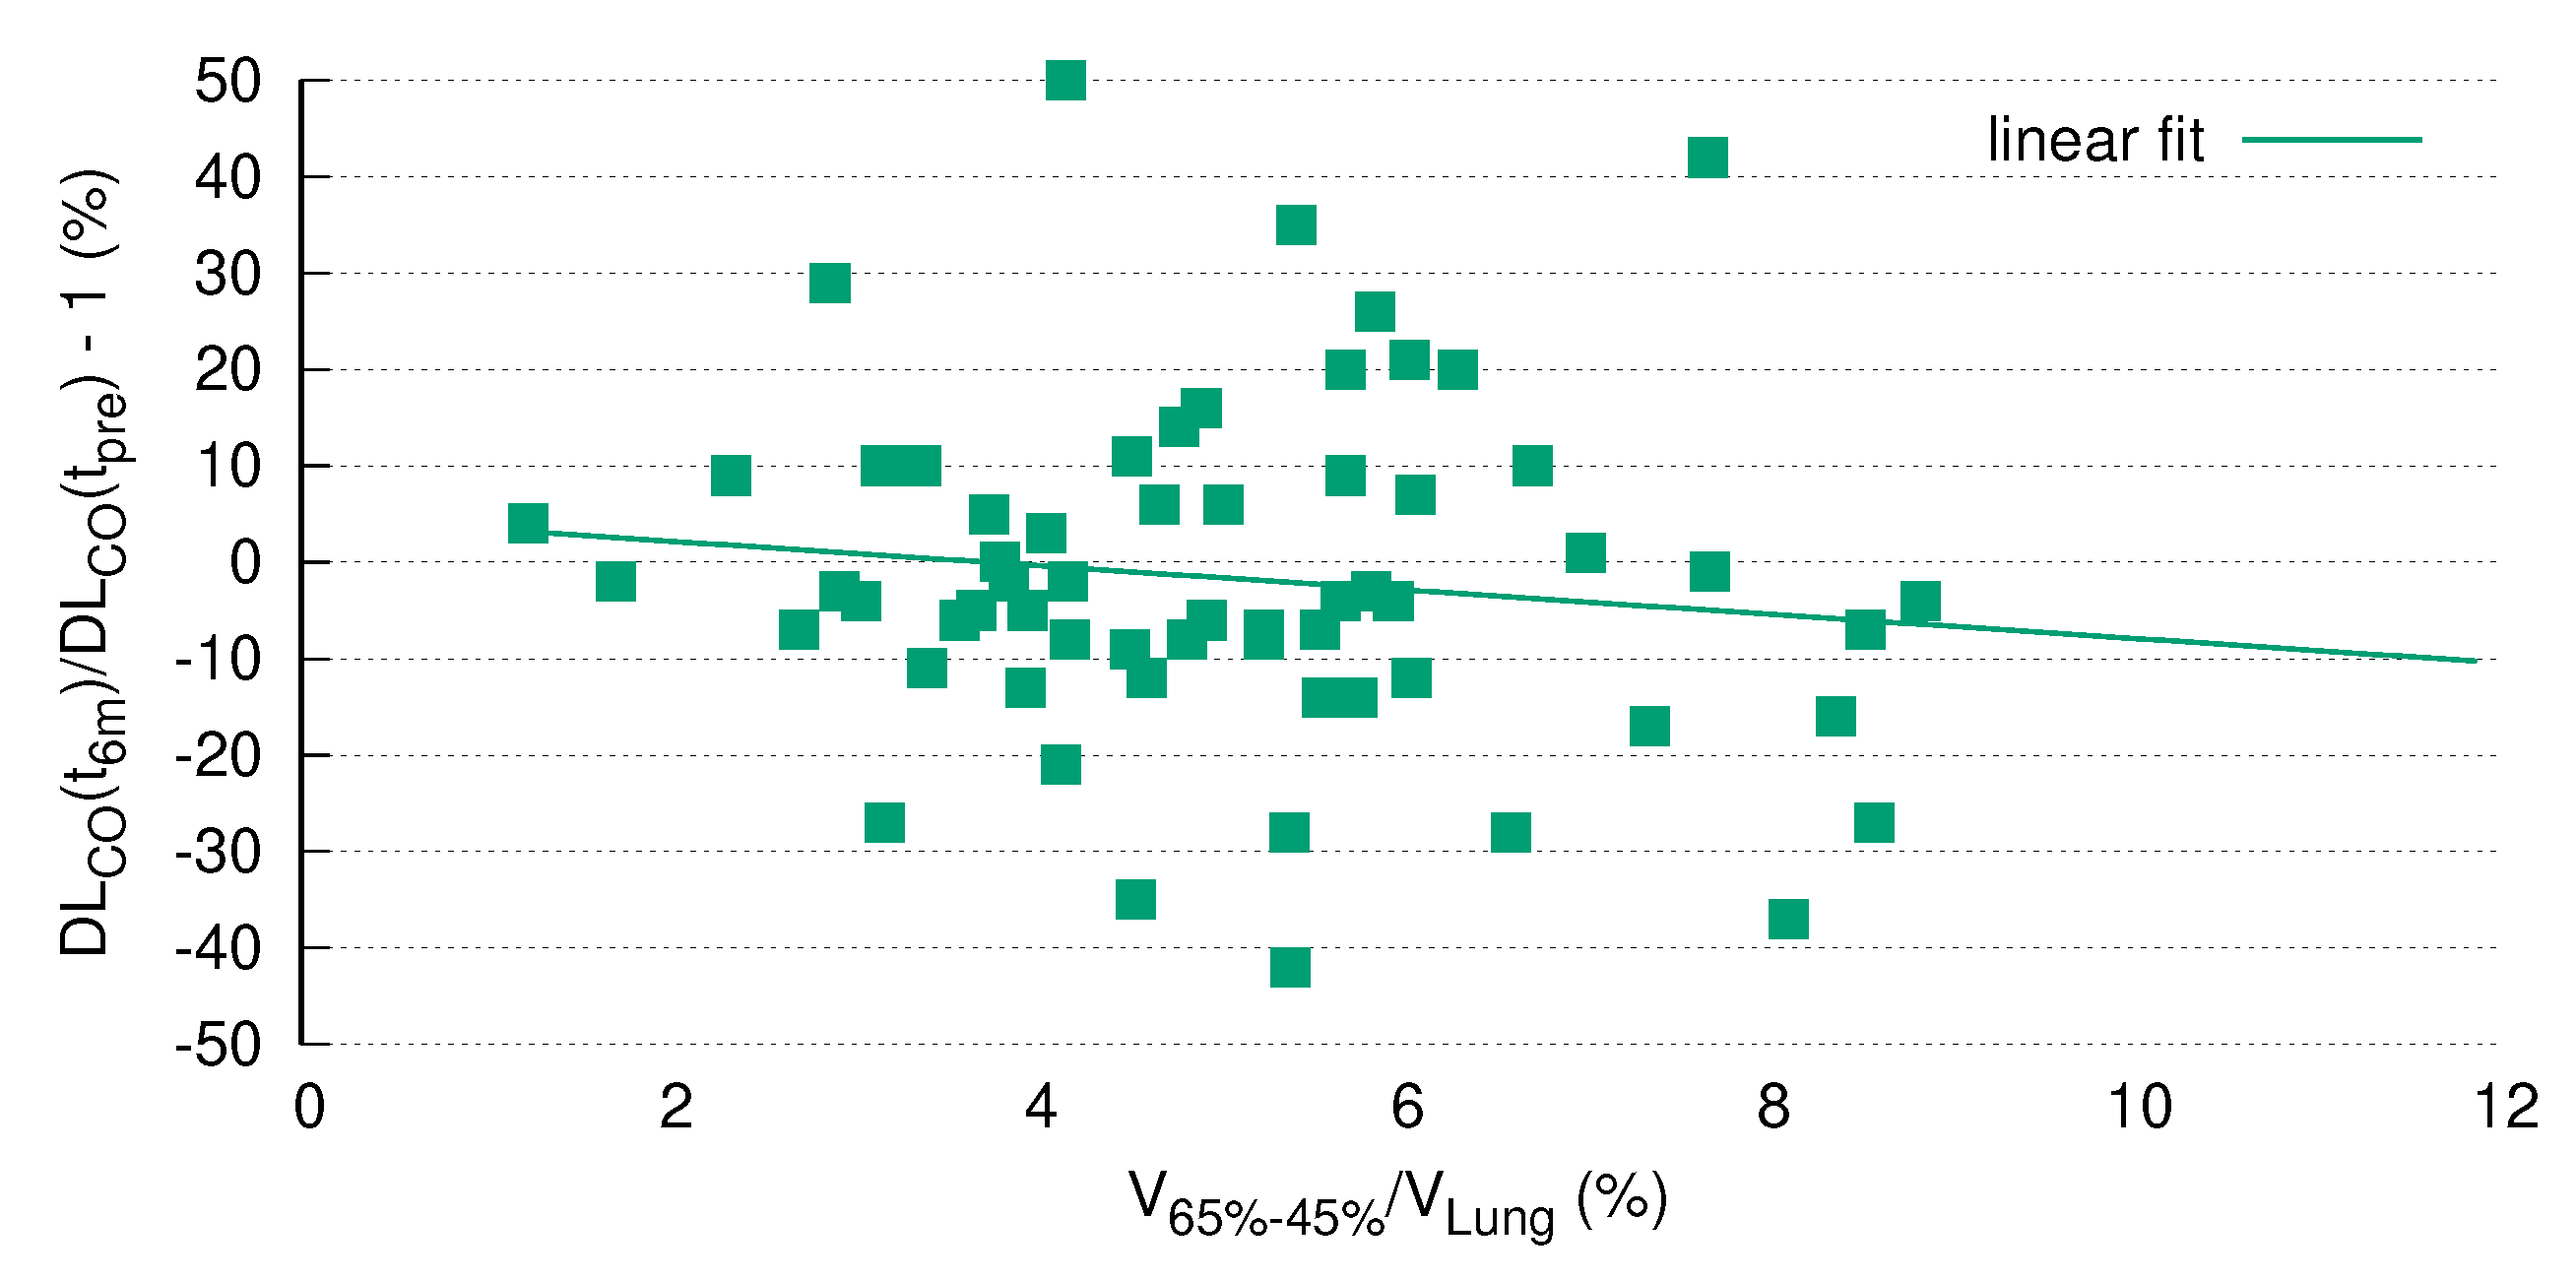

3.5. DL Correlates with V

3.7. DL after RT Is Predicted by V

4. Discussion